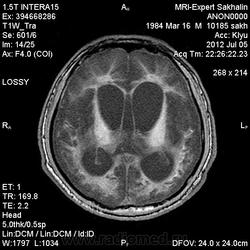

1 случай -локальная гемиатрофия.2 случай-диффузная.

Молодой человек после автомобильной аварии.3 года лежит.Двигаются только глаза.Зрелище душещипательное.

Евгений, конечно же, мои случаи не являются "чистой" атрофией-согласна.Мне пока не встречались случаи болезни Пика, Альцгеймера и другие "чистой воды" атрофии.Второй случай- состояние после длительной комы вследствие автодорожной травмы 3 года назад.Пациент проходил исследование в прошлом году , в этом родители привезли на динамику.